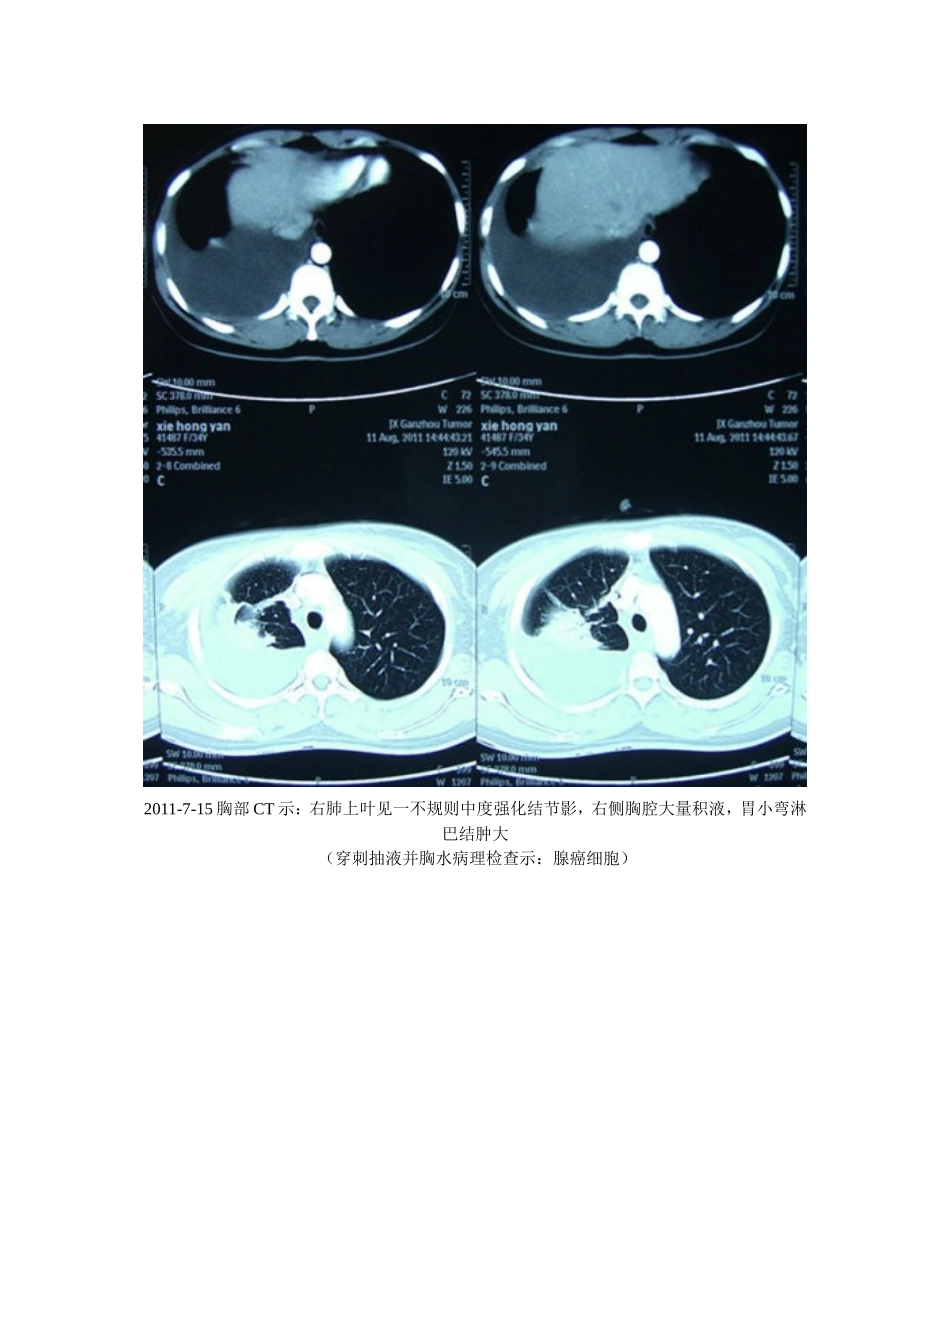

癌性胸腔积液----临床案例剖析----中华宋庆龄基金会特聘专家.。杨登平临床案例剖析1肺腺癌伴胸腔积液【病史摘要】:女性,34岁。患者于2011年7月份无明显诱因出现右侧胸痛,呈持续性痛,无发热盗汗及胸闷气紧,无头晕头疼,无恶心呕吐及其他不适。曾在当地医院治疗(具体治疗不详),症状无明显好转。于20011-7-9至2011-7-13在赣南医学院附属医院行胸部CT示右侧胸腔积液。胸水检查示:见腺癌细胞。于2011-7-15日转入赣州市三六二肿瘤医院行胸腔穿刺抽液及行一程化疗,化疗方案为:培美曲塞+顺铂;化疗过程顺利。于2011-8-11行第二程化疗,入院后完善相关检查,胸部CT示:右肺上叶见一不规则中度强化影,右侧胸腔大量积液,胃小弯淋巴结肿大;行胸腔穿刺抽液及对症支持治疗,予以吉西他滨+顺铂方案行二程化疗,患者除中度厌食及疲乏外,其他症状好转,于2011-8-25出院。出院二周余右胸又出现持续性疼痛并有牵扯感,到当地县医院胸腔X光扫示:右侧胸腔大量积液。遂放弃第三程化疗,于2011-9-28经人介绍到梅州天行健养生食疗中心进行食疗控制胸水和病情。患者疲乏、消瘦、厌食、咳嗽、脱发、右胸持续性疼痛并牵扯感明显。一:用加味开胃汤升提胃气,激活免疫。二:用牦牛蹄筋硬蛋白重建基质屏障(ECM,包围圈),修复侵袭破溃的胸膜。三:喝小米粥等粗粮,过午不食,保持气化和吸收。四:喝鲤鱼牛肉汤增强营养。五:喝鲜榨果汁。六:严格遵守饮食禁忌及养生之道等。20余天后出现饥饿感,症状好转。坚持3个月后于2011-11-28在梅州市人民医院行CT检查报告示:“右肺癌伴胸腔积液”治疗后复查,与2011-8-11日外院CT片对比,现片示:右肺上叶片影较前缩小、淡薄,纵膈窗大小约2.5*1.4cm,其周围支气管扩张,并见斑片状模糊影分布,病灶较前增多。:右肺上叶尖段纵膈旁可见一小结节,较前稍缩小。右肺中叶少许条索状影,边界清。双肺纹理粗乱,肺透亮度增高。双肺门未见增大。纵膈内未见肿大淋巴结。右胸积液已吸收,左侧胸腔未见积液。余大致同前。意见:1、“右肺癌伴右侧胸腔积液”治疗后复查,右肺上叶片块影及小结节较前有所缩小,右侧胸腔积液已吸收;2、考虑右肺上叶支气管扩张合并感染;3、慢性支气管炎、肺气肿征象,右肺中叶少许纤维灶。2011-8-11复查CT检查报告。(穿刺抽液并一程化疗后)2011-7-15胸部CT示:右肺上叶见一不规则中度强化结节影,右侧胸腔大量积液,胃小弯淋巴结肿大(穿刺抽液并胸水病理检查示:腺癌细胞)2011-11-28CT示右侧胸腔积液已吸收,左侧胸腔未见积液。2011-11-28胸部CT示“右肺癌伴右侧胸腔积液”治疗后复查,右肺上叶片块影及小结节较前有所缩小,右侧胸腔积液已吸收。【评述】:肺癌的细胞分为两大型:小细胞肺癌和非小细胞肺癌,非小细胞肺癌(NSCLC)又可以分为鳞癌、腺癌、大细胞等亚型。小细胞肺癌的特点是多见男性青少年,生长快,18天倍增一次,放化疗非常敏感,停药易复发,非常容易脑转移,化疗必须做到12次以上且愈后不佳。得了肺癌是不幸的,实话实说,得了肺腺癌是不幸中的不幸,肺腺癌的特点是多见女性和不抽烟的男性,小腺癌,大转移,转移早,复发快,脑转移,骨转移,非常容易出现胸水,放化疗不敏感,预后差,死亡率高。本案穿刺抽液病理诊断是肺腺癌,胸膜转移已有大量的癌性胸水。两次穿刺抽液并两次化疗,而反复大量胸水未能控制(化疗不敏感),并出现肺实质性损伤(慢性支气管炎、肺气肿征象,右肺中叶少许纤维灶等)副作用。本案例从2011-8-26日--2012-8-29日到本中心控制病变,CT提示现胸腔积液已完全吸收,病灶结节等缩小,说明癌性积液等病变已基本控制。临床表明养生食疗及牦牛蹄筋硬蛋白对恶性实体瘤控制病情是有益的、有效的。值得在原发肿瘤及控制肿瘤的复发和转移的基础研究与临床实践中作理性的尝试和探索。